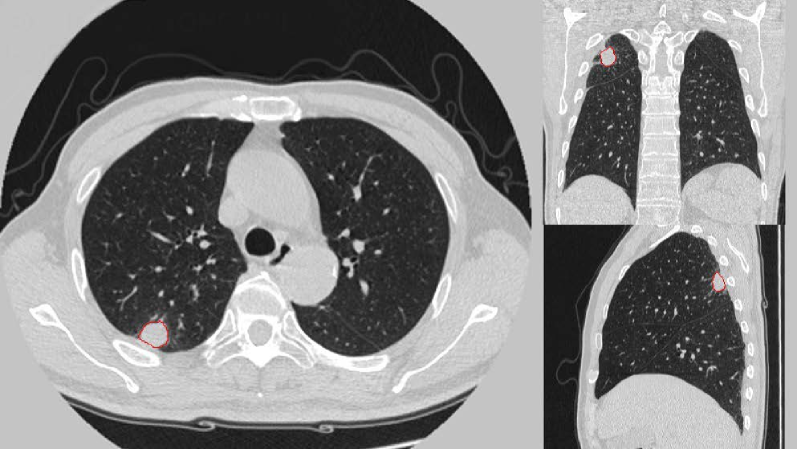

The nodule segmentation is performed semi-automatically, that is, the radiologist manually locates the nodule and examines the final segmentation results, and the contour of the nodule is automatically delineated by the computer programs. First, a trained U-net (R-231) [hofmanninger2020] was employed to remove regions outside the lungs in CT, thereby separating the juxta-pleural nodules from the lung boundary. Second, all images were resampled to 1×1×1-mm voxel size using cubic interpolation. Third, the boundary of nodule was described by Active contour model [chan2001] and refined by morphological methods. Finally, we corrected the segmentation based on the radiologist’s feedback on the results. Figure˜2 shows an example of segmentation results in three views.